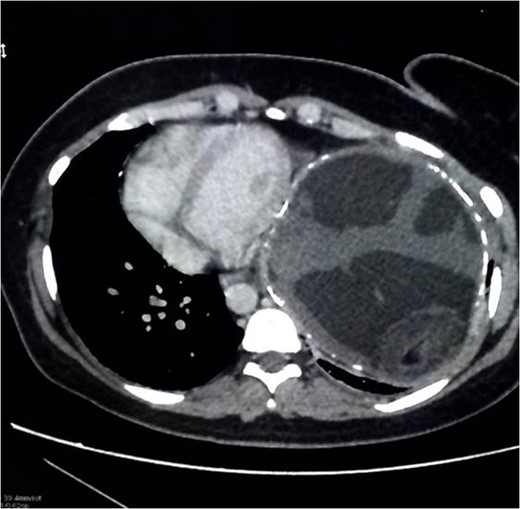

Chest x-ray showed well-defined huge opacity of most left hemithorax with a shift of mediastinum to the right (Fig. 1). CT chest/abdomen/pelvis with IV contrast revealed 20 × 15 × 18 cm3 well-defined mixed cystic lesion within the left lung containing multiple parts of the heterogeneous density with soft tissue elements and fat content. It also showed spots of wall calcification, where the lesion probably originated from the mediastinum, involving most of the left hemithorax. The mass compressed the mediastinal structures, great vessels, and airways (Fig. 2). It is surrounded by a consolidation collapsed with a marked shift of mediastinum to the right side (Figs 2 and 3). No mediastinal lymphadenopathy and the right lung was clear. The spleen was enlarged with multiple cysts that varied in size with no significant enhancement post IV contrast in arterial and portal phases (Figs 2 and 4). The liver was unremarkable. Hematological tests were within normal limits. Mantoux test and Sputum culture were negative.

The decision was to perform a standard left anterolateral thoracotomy to remove the thoracic tumor after expiration because the cystic tumor was found to be very congested and vulnerable to rupture during the extraction (Fig. 5). It emptied a large amount of thick, white/yellowish fluid and hair particles (Fig. 6). The size of the tumor was extremely large, although no invasion to the mediastinum, vessels or to the airway had occurred. The tumor detached from the phrenic angle, diaphragm and all of the surrounding structures without any bleeding, air leak or complications. A laparoscopic splenectomy was done in the same session, and the spleen was extracted through the old cesarean incision scar for cosmetic purposes; the spleen shows multiple cysts on both visceral and diaphragmatic surfaces (Figs 7 and 8).